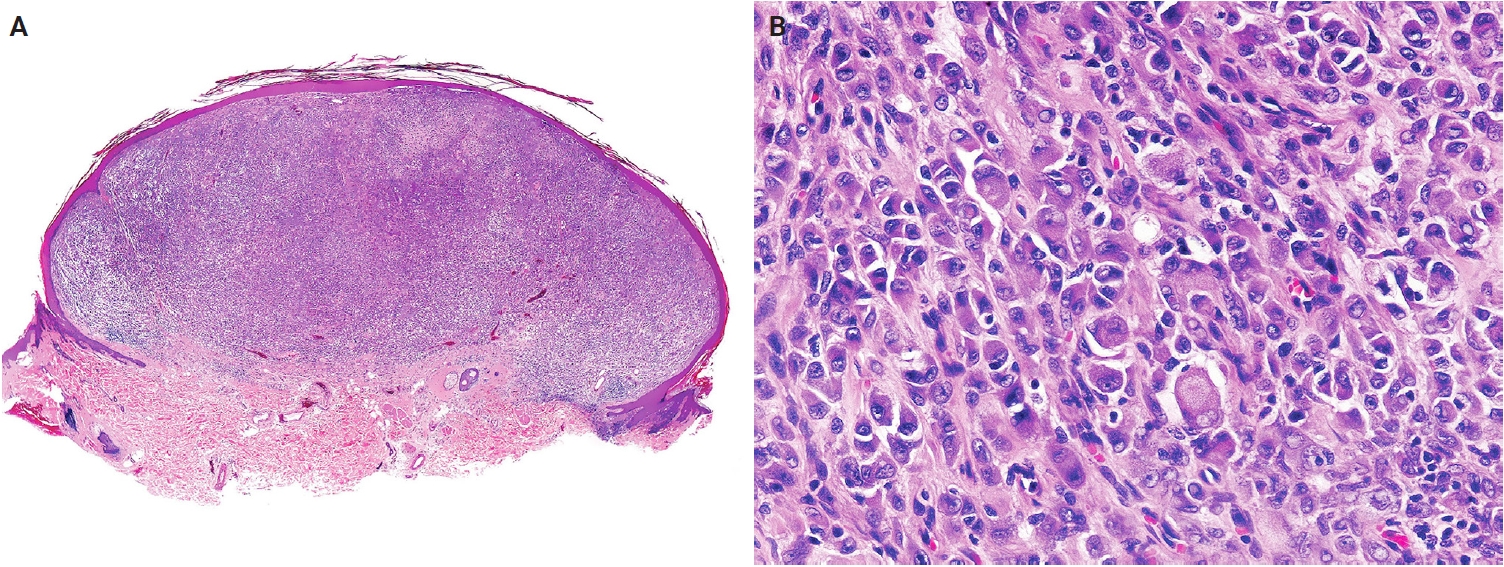

Histologically, EFH is typically well-circumscribed, and exophytic lesions often exhibit an adnexal collarette (Fig. 13A). The tumor consists of uniform epithelioid cells with vesicular nuclei, small nucleoli, and pale eosinophilic or amphophilic cytoplasm (Fig. 13B). Binucleated forms are frequently observed. Thin-walled vessels are common, often with perivascular accentuation of tumor cells. Morphological variants include chondroblastoma-like pericellular calcification [279,282] and spindle cell-predominant forms [283,284]. Immunohistochemically, ALK is overexpressed in approximately 90% of cases [285], with D5F3 or 5A4 clones demonstrating higher sensitivity than the ALK1 clone [276,286]. EMA is positive in approximately 65% of cases [286], and CD30 expression may also be present.

Fig. 13.

Epithelioid fibrous histiocytoma. (A) Scanning magnification shows a well-circumscribed, dome-shaped dermal tumor with an adnexal collarette. (B) The tumor is composed of epithelioid cells with round to oval vesicular nuclei, small nucleoli, and abundant eosinophilic or amphophilic cytoplasm. Reprinted from Requena and Hornick. Epithelioid fibrous histiocytoma. In: WHO Classification of Tumours Editorial Board, ed. WHO classification of tumours: skin tumours. 5th ed. [273], with permission from IARC Press.